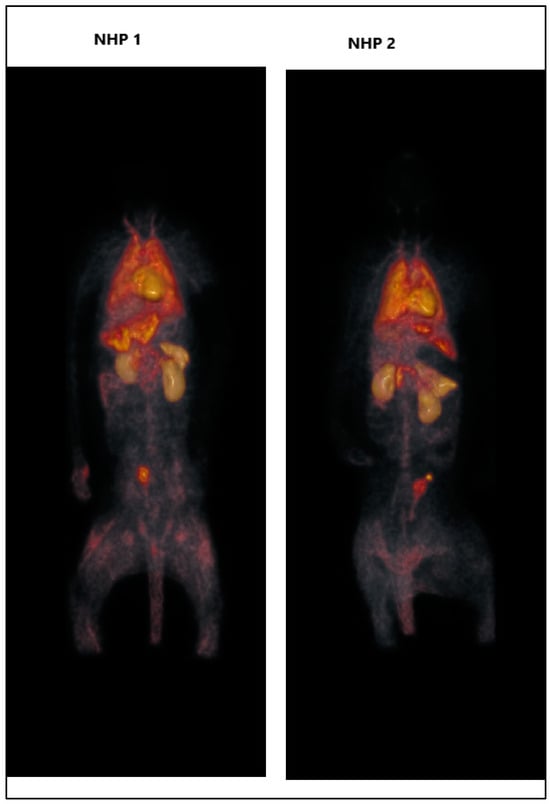

- Dosimetry Assessment: To ensure the safe and effective application of [11C]Kln83 in human studies, we conducted dosimetry assessments using data obtained from whole-body PET scans in non-human primates (NHPs). This crucial step involved meticulously evaluating the distribution and clearance of the radioligand within the NHPs’ bodies, allowing us to calculate the radiation dose received by various organs and tissues. The data obtained from these assessments will be essential for determining the optimal dosage for human studies, minimizing radiation exposure while maximizing diagnostic efficacy.

2.2. Whole-Body PET

3.4. Whole-Body PET Measurements in NHP